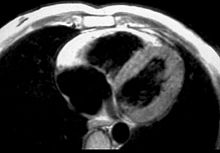

MRI in a patient affected by ARVC/D (long axis view of the right ventricle): note the transmural diffuse bright signal in the RV free wall on spin echo T1 (a) due to massive myocardial atrophy with fatty replacement (b).

In vitro MRI and corresponding cross section of the heart in ARVD show RV dilatation with anterior and posterior aneurysms (17-year-old asymptomatic male athlete who died suddenly during a soccer game).

Fatty infiltration of the RV free wall can be visible on cardiac MRI. Fat has increased intensity in T1-weighted images. However, it may be difficult to differentiate intramyocardial fat and the epicardial fat that is commonly seen adjacent to the normal heart. Also, the sub-tricuspid region may be difficult to distinguish from the atrioventricular sulcus, which is rich in fat.

Cardiac MRI can visualize the extreme thinning and akinesis of the RV free wall. However, the normal RV free wall may be about 3 mm thick, making the test less sensitive.